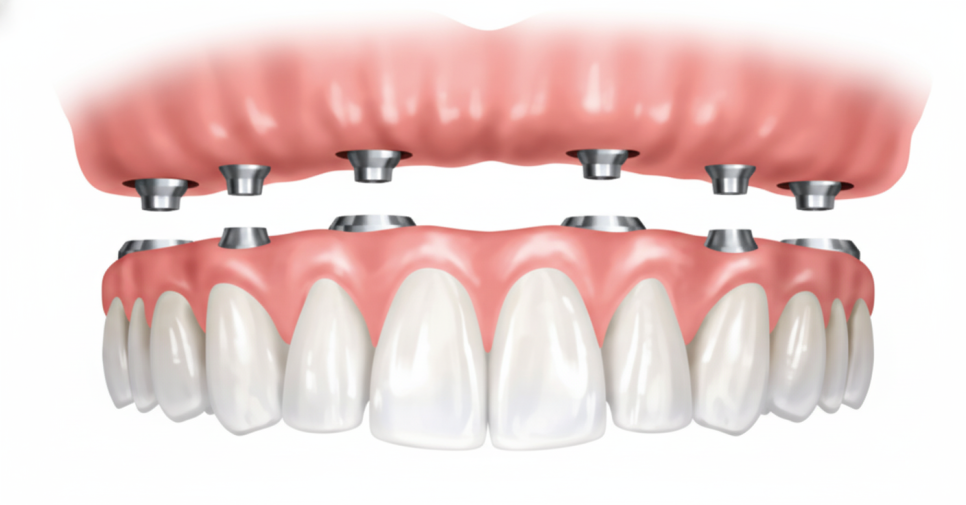

오버덴쳐는 최소한의 개수로

임플란트를 식립한 뒤에,

틀니와 연결할 수 있도록 만들어

지지력을 높인 보철입니다.

일반 틀니가 잇몸 위에

단순히 얹혀 있는 구조라면

오버덴쳐는 고정 장치가 있어

안정적으로 자리를 잡을 수 있죠.

overdenture는

유지 장치의 형태에 따라

여러 종류로 나뉘게 됩니다.

✅ 바(bar) 타입입니다.

여러 개의 임플란트를 바 형태의

금속 구조물로 연결하고

그 위에 틀니를 장착하는 방식입니다.